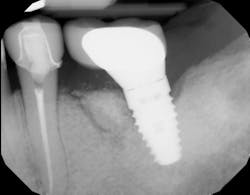

Immunomodulatory medications—used for rheumatoid arthritis, psoriasis, IBD, and lupus—represent a growing contributor to MRONJ (figures 1a and 1b).7,8